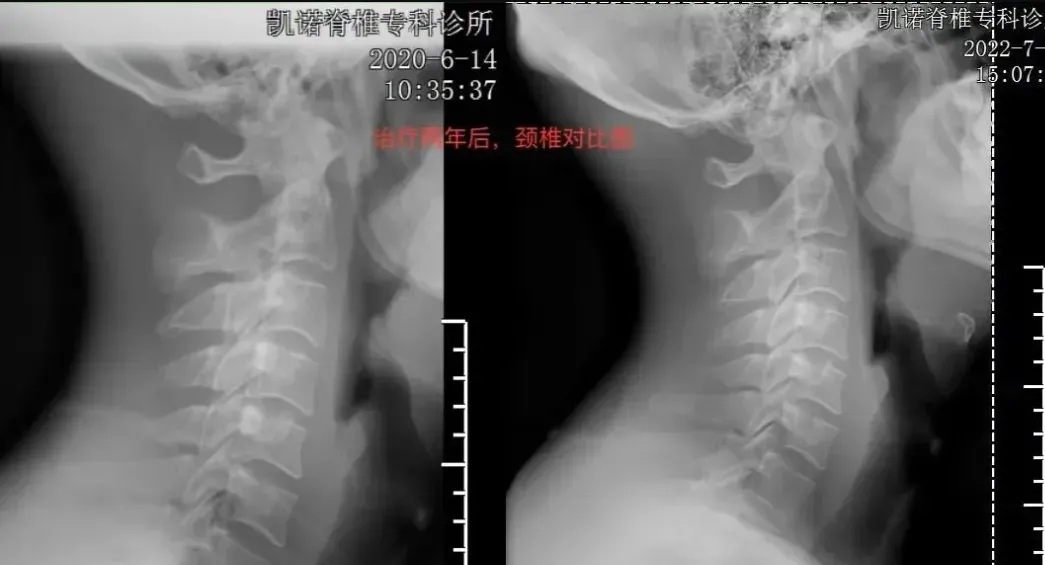

美式整脊与其他治疗方式相比较,尤其对于没有达到手术指标的脊椎问题,优于常规治疗方式,效率高,见效快,对脊椎保健和脊椎病的预防具有长远的作用。

本技术直接作用于不正的脊椎椎体,迅速的调整恢复正常的状态与结构,以达到矫形,镇痛,去除症状的目的

美式整脊技术更加注重骨骼结构的调整,而非单独处理软组织的问题,强调骨正筋柔,大多数人可以通过3-7次的矫正有效缓解疼痛。